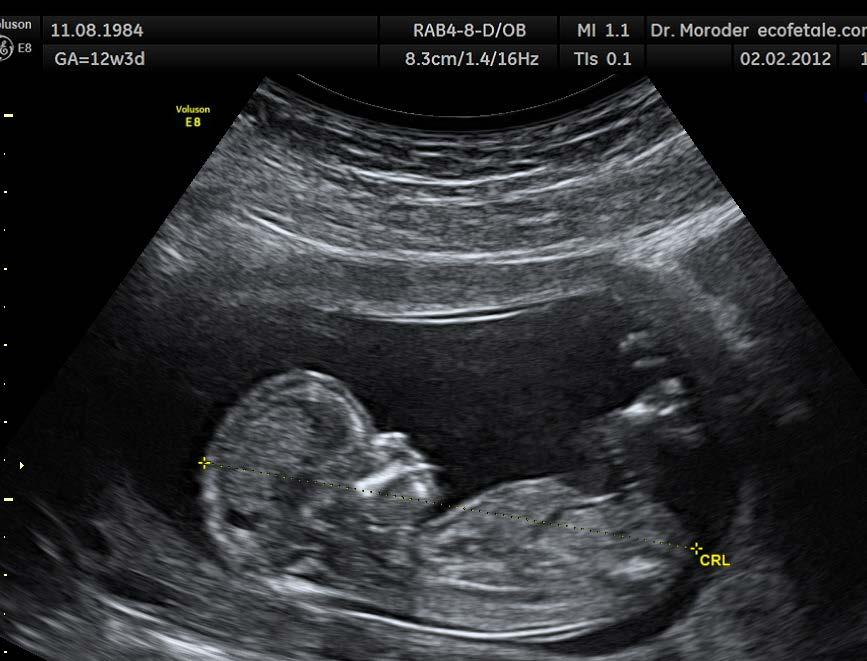

Medicinsk billeddannelse - stiller skarpt på din sygdom og behandling

Sundhedssektoren er forbruger af noget af den mest avancerede højteknologi til diagnostik, monitorering og behandling ikke mindst i forbindelse med patientspecifikke forløb. Samtidig er markedet for sundhedsteknologi globalt ekspanderende,” siger DTU´s prorektor Rasmus Larsen.